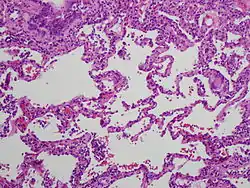

| תמונה היסטולוגית של דלקת ריאות מרגישות יתר כרונית | ||

מאפיין היסטולוגי נפוץ בדלקת ריאות מרגישות יתר הוא גרנולומות לא גבינתיות, סמוך לדרכי האוויר הקטנות, שאינן מתוחמות היטב. עוד נצפים תסנינים, לימפוציטריים ברובם, בפיזור כתמי בנאדיות וברקמת החיבור (אינטרסטיציום). בדלקת כרונית מופיעים שינויים לייפתיים מקומיים, כאשר במחלה מתקדמת הם הופכים להיות נרחבים וחמורים עם מאפייני חלת דבש.

התמונה ההיסטולוגית של גרנולומות בריאה מופיעה גם במחלות אחרות, דוגמת סרקואידוזיס, אך סרקואידוזיס היא מחלה עם ביטוי בשאר מערכות הגוף, והגרנולומות בה מוגדרות היטב, בניגוד לדלקת ריאות מרגישות יתר.